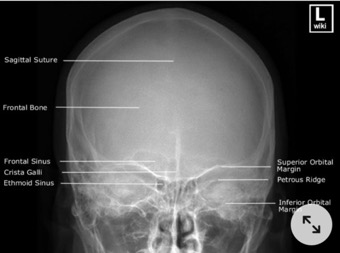

4. INCIDENCE DE FACE DROITE (NEZ-FRONT) (ROCHERS DANS LES ORBITES)

Etude de la voute